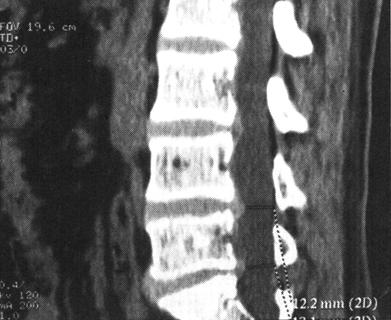

图7-17 T12压缩性骨折并脊髓横断性损伤:T1W(a)和T2W(b)矢状面扫描,可见T1压缩变扁,T11以上向前移位,脊髓呈横断性改变。椎间盘及脊柱前纵韧带下血肿。冠状面脊柱两侧亦见高信号出血